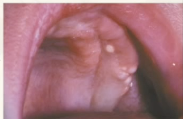

eruption cyst characteristics

no radiographic presentation

bluish

common in kids